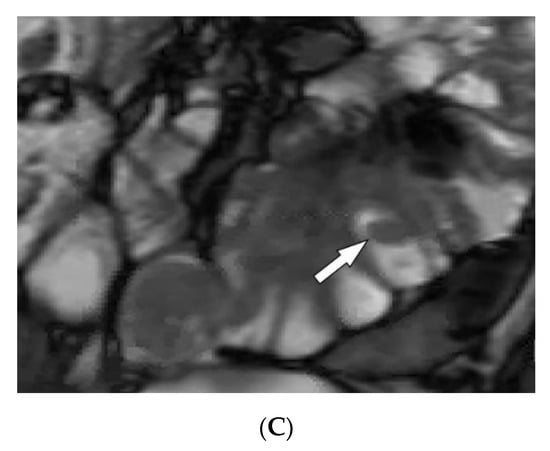

| Polyarteritis nodosa | Palpable purpura Painful nodules on lower legs Livedo reticularis Medium-sized artery vasculitis | Microaneurysms and constrictions of medium-sized arteritis (beaded appearance) |